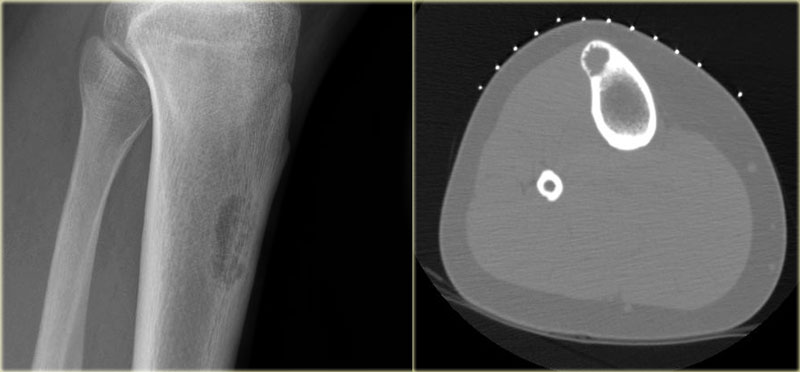

ABC (6) - atypical case

On the left two different patients with an intracortical or subperosteal osteolytic well-defined lesion in the tibia.

The lesion on the far left was thought to be an adamantinoma because of the localisation in the anterior tibial cortex.

At biopsy it proved to be an ABC.

The image on the right is an adamantinoma.